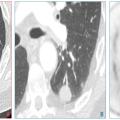

4. « La maladie est décelable pendant une phase de latence ou au début de la phase clinique et l’histoire naturelle de la maladie est connue » :le cancer du poumon est décelable avant d’être cliniquement parlant, pendant une durée variable, dépendant du temps de doublement du cancer. Il s’agit le plus souvent d’un nodule infracentimétrique solide, non calcifié, ou en verre dépoli, totalement asymptomatique, qui précède de plusieurs années le développement de masses pulmonaires plus grosses ou de cancers métastatiques (fig. 1).